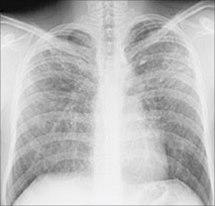

Sarkoidose i lungerSymptomene kan gi mistanke, men oftest vil det være røntgenbilder som viser de typiske forandringene i lungene (se bilde). For å kunne stille en sikker diagnose er det likevel nødvendig med mikroskopisk undersøkelse av en vevsprøve fra lungene, noe som vanligvis blir tatt i forbindelse med bronkoskopi. På bakgrunn av røntgenbildene kan sarkoidose inndeles i ulike stadier fra stadium I (minst uttalt) til stadium IV (mest uttalt).